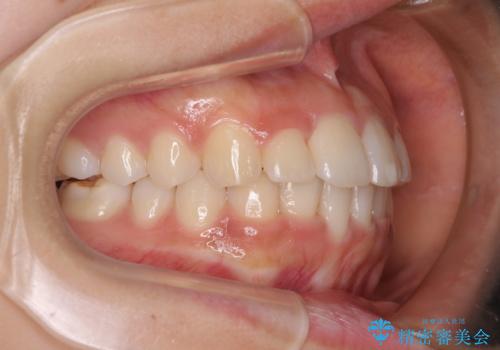

- 飛び出した前歯と全体的なデコボコを気にして来院された患者様です。

ワイヤーでもマウスピースでも治療可能でしたが、自己管理の重要なマウスピース矯正は自分には向かないとのことで、ワイヤー矯正で治療することとしました。

上下歯列全体を後方に移動させるため、親知らずは全て抜歯することにしました。